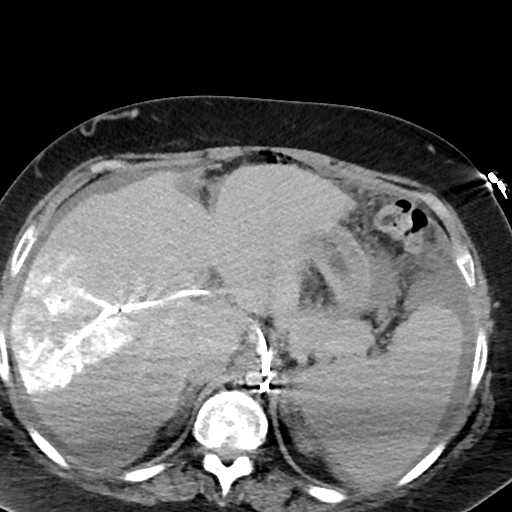

Case 1

79 M with PMH of CKD, HLD, prostate cancer s/p prostatectomy + radiation presenting with feelings of fogginess, upset stomach, and diarrhea. Originally worked up at OSH, imaging concerning for a hepatic mass.

148/77 mmHg / 95 bpm / 15 breaths/min / 98.1°F / 98 ORA

sclera anicteric, no jaundice

AST 112, ALT 34, Alk Phos 202, CEA 2, CA 19-9 4